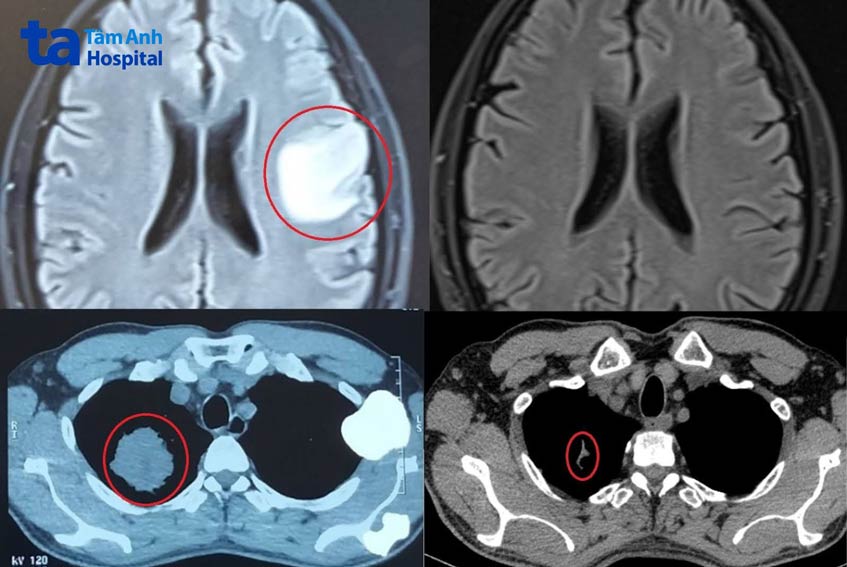

Như ông Duy, 55 tuổi, đến khoa Ung bướu, Bệnh viện Đa khoa Tâm Anh Hà Nội khám trong tình trạng ho nhiều, nửa người bên phải tê yếu, tiền sử hút thuốc lá hơn 40 năm. Sau khi thực hiện các xét nghiệm, chụp cắt lớp vi tính phổi và cộng hưởng từ não, bác sĩ kết luận ông Duy bị ung thư phổi giai đoạn cuối, di căn não, tiên lượng rất xấu. Nếu không điều trị, người bệnh chỉ sống được tối đa 6 tháng.

Kết quả chụp cộng hưởng từ vào tháng 8 năm nay cho thấy u não 3×4 cm biến mất. Trên phim chụp cắt lớp vi tính, u phổi phải 4×6 cm tương đương quả trứng gà chỉ còn là một dải xơ. Ung thư phổi là một trong những loại có độ ác tính cao, tốc độ tử vong nhanh, nhất là giai đoạn di căn não. “Kết quả điều trị của ông Duy rất đáng ngạc nhiên”, bác sĩ Khiêm nói.